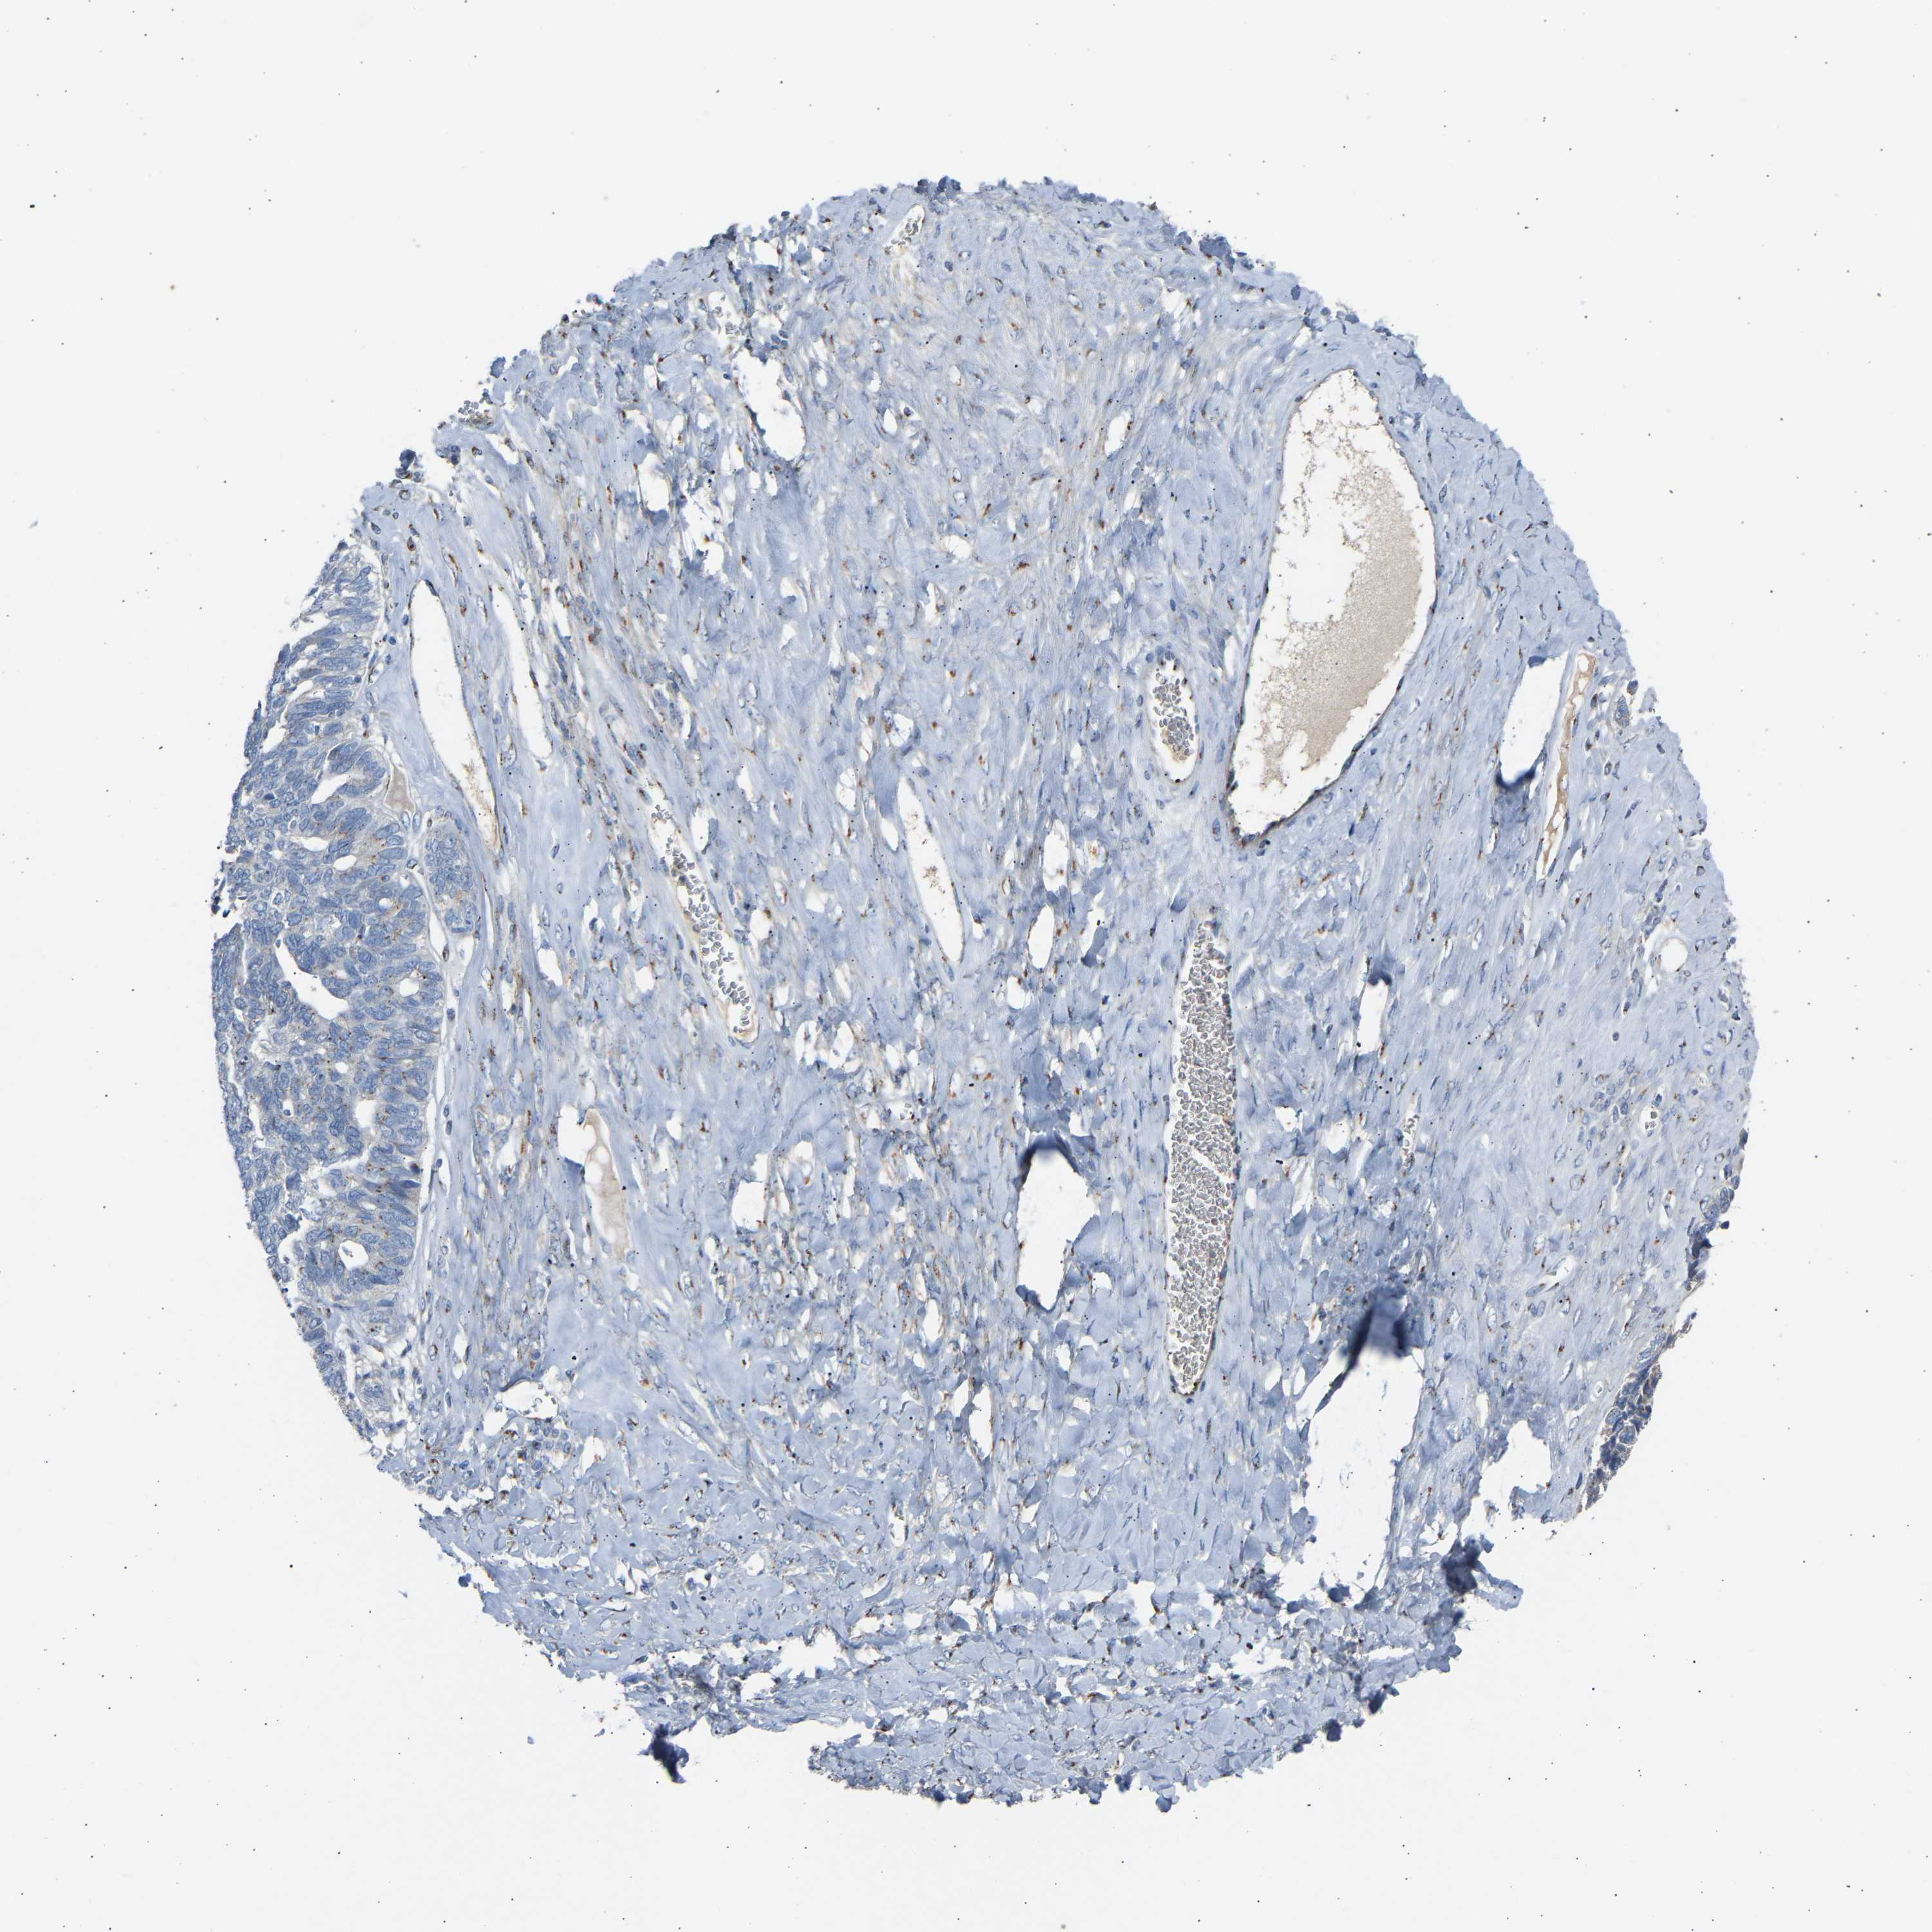

OVARIAN CANCER - Protein expressioni

A mouse-over function shows sample information and annotation data. Click on an image to view it in a full screen mode. Samples can be filtered based on level of antibody staining by selecting one or several of the following categories: high, medium, low and not detected. The assay and annotation is described here.

Note that samples used for immunohistochemistry by the Human Protein Atlas do not correspond to samples in the TCGA dataset.

Antibody stainingi

Antibody staining in the annotated cell types in the current human tissue is reported as not detected, low, medium, or high, based on conventional immunohistochemistry profiling in selected tissues. This score is based on the combination of the staining intensity and fraction of stained cells.

Each image is clickable and will lead to virtual microscopy that enables deeper exploration of all samples and also displays staining intensity scores, fraction scores and subcellular localization as well as patient and tissue information for each sample.

Antibody HPA020060

Staining

High

Medium

Low

Not detected

Intensity

Strong

Moderate

Weak

Negative

Quantity

>75%

75%-25%

<25%

None

Location

Nuclear

Cytoplasmic/membranous

Cytoplasmic/membranous,nuclear

Cystadenocarcinoma, serous, NOS

Carcinoma, endometroid

Cystadenocarcinoma, mucinous, NOS

Carcinoma, NOS